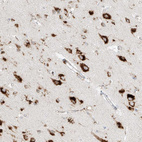

Immunohistochemical staining of human prostate shows strong granular cytoplasmic positivity in glandular cells.